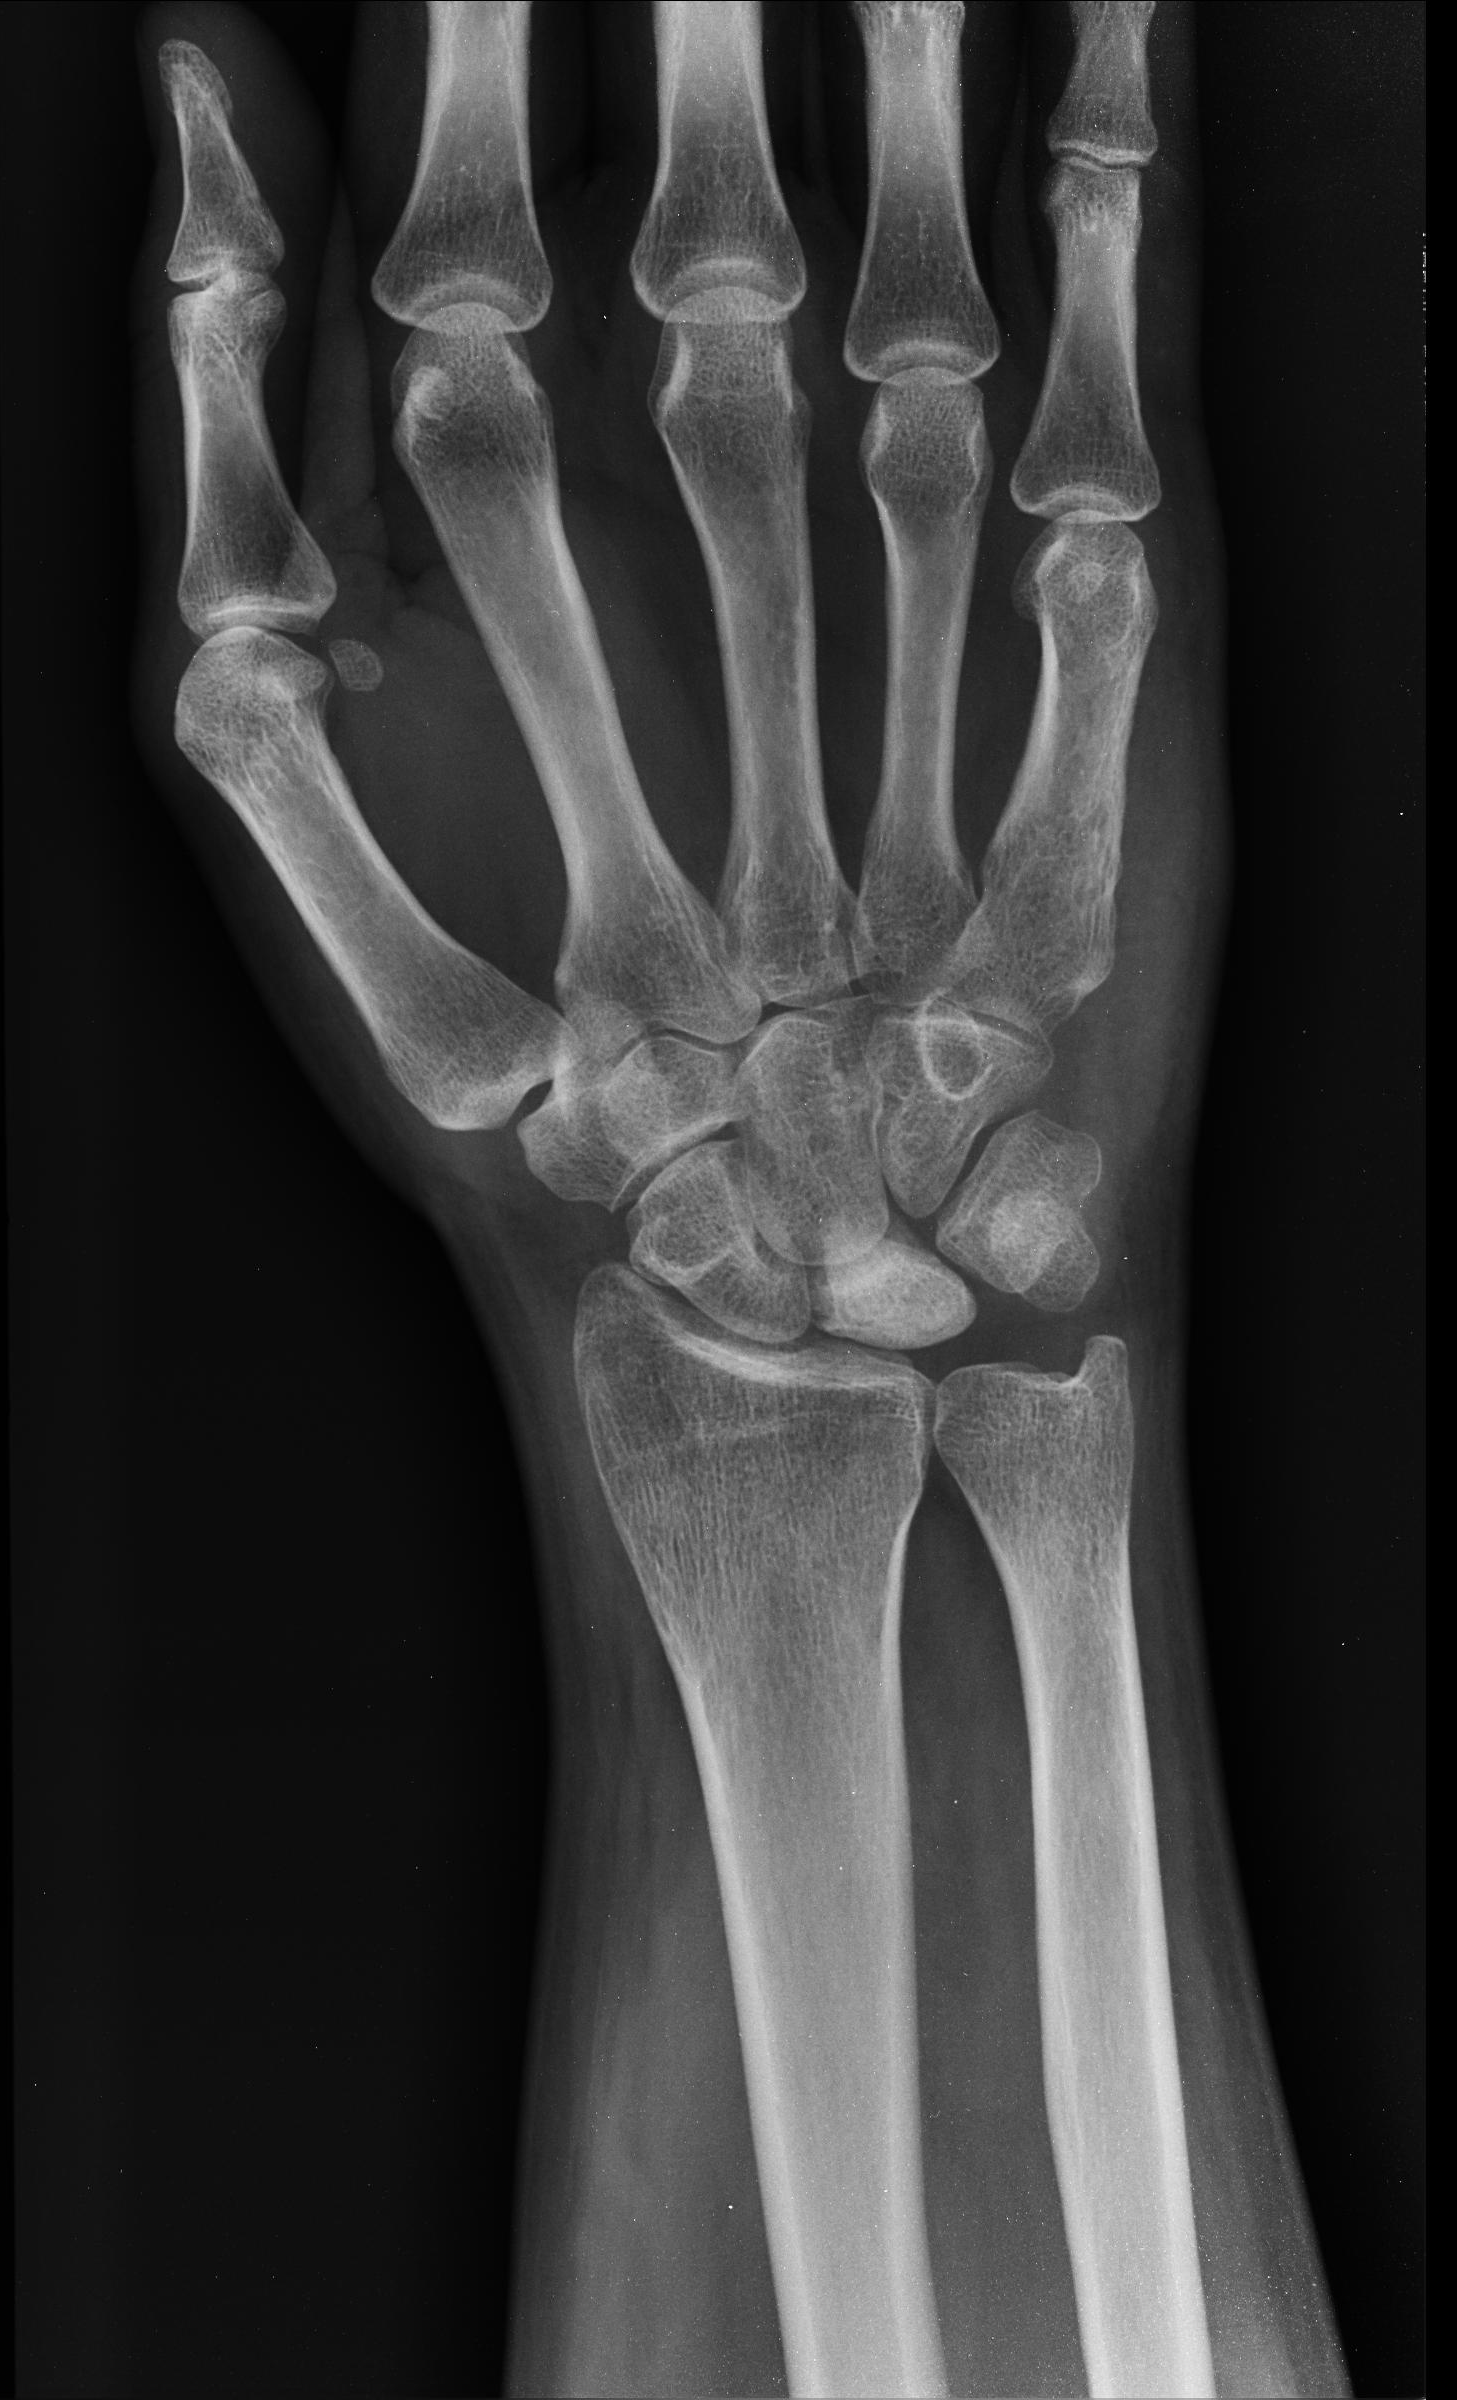

• Avascular necrosis of the lunate

• Associated with negative ulnar variance (ulna is shorter than the radius)

• XR = sclerosis and flattening of lunate